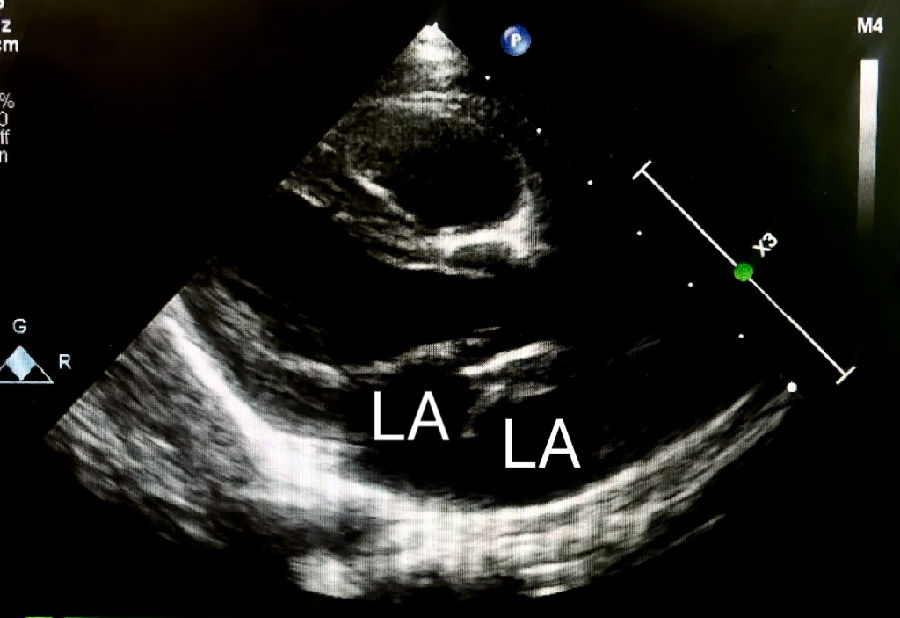

三房心是一种罕见的先天性心脏异常,于1868年被首次描述,仅占所有先天性心脏畸形的0.1%至0.4%,大多数患者在婴儿期或儿童期即被诊断出,成人的病例很少,可以涉及左心房或右心房,其定义为心房(左或右)内的异常隔膜,导致向各自的心室流入阻塞,它更常见于左心房。它要么以孤立的经典形式存在,要么可能与简单或复杂的先天性心脏异常有关。男性和女性之间没有发现该疾病发病率有明显差异,文献中也没有描述相关的遗传疾病。在高达80%的儿科人群中,该异常可能与其他先天性心脏病变有关,最常见的是房间隔缺损和肺静脉异位引流。

在体检中,有时可以通过听诊检测到心脏杂音。杂音的强度取决于血流通过隔膜的速度。超声心动图(经胸或经食道)是评估三房心解剖学和生理学的主要成像方式,彩色多普勒下的花色血流信号通常表示血流的加速和湍流的出现,这表明可以通过血流通过隔膜时可能有梗阻。经食管超声心动图的成像优于经胸超声心动图,可以明确的诊断三房心,并区分真正的左心房、左心房附属物以及隔膜的形态和梗阻程度。三维超声心动图是一种新的诊断工具,可以给临床提供额外的信息,能够明确隔膜的大小、位置和开口数量等。